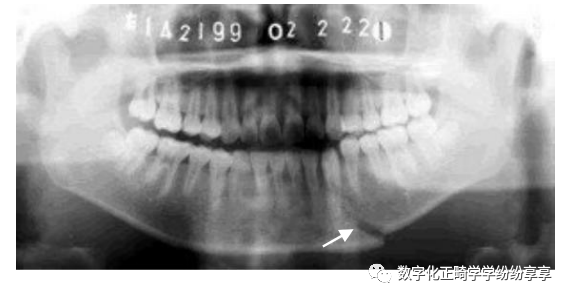

骨折问题:

颏部骨折

曲面断层片怎么看正畸【曲面断层片(全景片)】如何解读和查看:牙周?牙体?牙髓?关节?_https://www.jmylbn.com_新闻资讯_第24张

颏孔区骨折

曲面断层片怎么看正畸【曲面断层片(全景片)】如何解读和查看:牙周?牙体?牙髓?关节?_https://www.jmylbn.com_新闻资讯_第25张